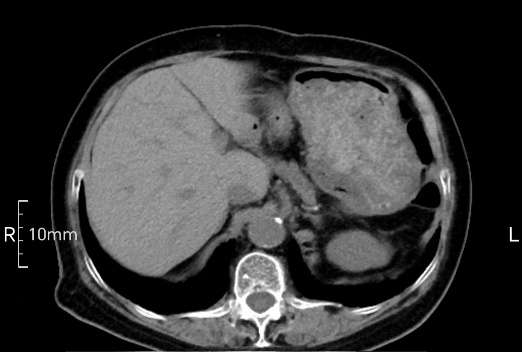

看看下面三幅便知遵醫(yī)囑的重要性。

完美禁食且喝飽飽,胃壁完美展現(xiàn)。

CT檢查前的“禁食”和“喝飽”,看似矛盾,實(shí)則合情合理,分工合作:空腹:是為了讓上腹部(肝膽胰脾腎等)的圖像清晰無干擾,并保障檢查安全。喝水:有效的充盈胃部和、腸道使圖像清晰呈現(xiàn)。兩者巧妙配合,都是為了給您一個(gè)最精準(zhǔn)的診斷結(jié)果。